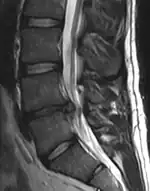

Herniated disc at C6–C7 level

Cervical disc herniations occur in the neck, most often between the fifth and sixth (C5–6) and the sixth and seventh (C6–7) cervical vertebral bodies. There is an increased susceptibility amongst older (60+) patients to herniations higher in the neck, especially at C3–4.[23] Symptoms of cervical herniations may be felt in the back of the skull, the neck, shoulder girdle, scapula, arm, and hand.[24] The nerves of the cervical plexus and brachial plexus can be affected.[25]

Click images to see larger versions

• Magnetic resonance imaging is the gold standard study for confirming a suspected LDH. With a diagnostic accuracy of 97%, it is the most sensitive study to visualize a herniated disc due to its significant ability in soft tissue visualization. MRI also has higher inter-observer reliability than other imaging modalities. It suggests disc herniation when it shows an increased T2-weighted signal at the posterior 10% of the disc. Degenerative disc diseases have shown a correlation with Modic type 1 changes. When evaluating for postoperative lumbar radiculopathies, the recommendation is that the MRI is performed with contrast unless otherwise contraindicated. MRI is more effective than CT in distinguishing inflammatory, malignant, or inflammatory etiologies of LDH. It is indicated relatively early in the course of evaluation (<8 weeks) when the patient presents with relative indications like significant pain, neurological motor deficits, and cauda equina syndrome. Diffusion tensor imaging is a type of MRI sequence used for detecting microstructural changes in the nerve root. It may be beneficial in understanding the changes that occur after herniated lumbar disc compresses a nerve root, and might help in differentiating the patients that need surgical intervention. In patients with a high suspicion of radiculopathy due to lumbar disc herniation, yet the MRI is equivocal or negative, nerve conduction studies are indicated.[44] T2-weighted images allow for clear visualization of protruded disc material in the spinal canal.